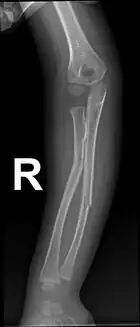

Diagnosis

Projectional radiography is generally preferable.